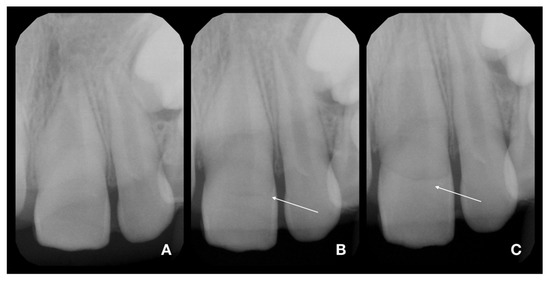

2.2. Partial Pulpotomy and Adhesive Reattachment of Tooth 11

2.3. Deep Pulpotomy and Adhesive Reattachment of Tooth 21 after Flap Reflection

2.4. Follow-Up